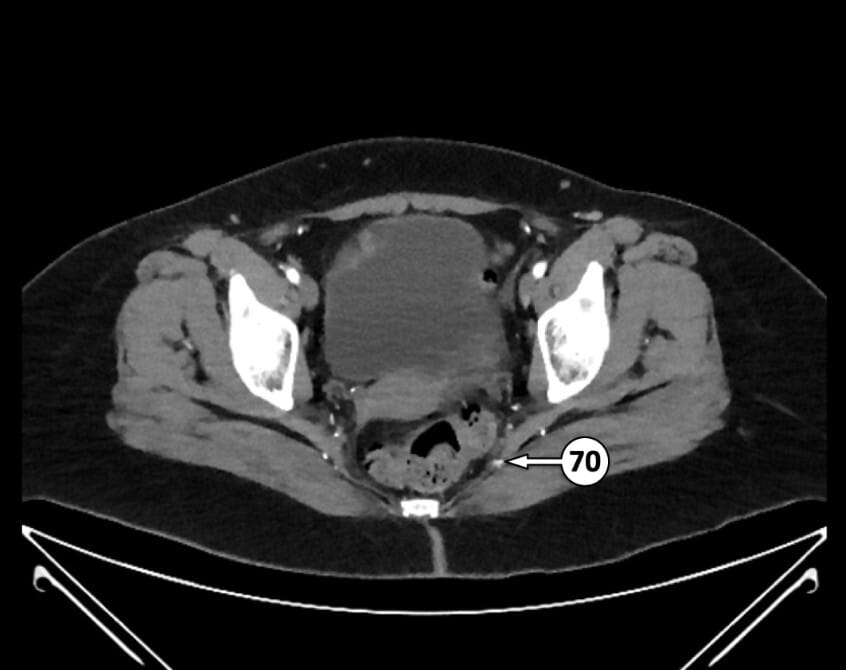

70. inferior gluteal artery (off posterior division of IIA, variant)